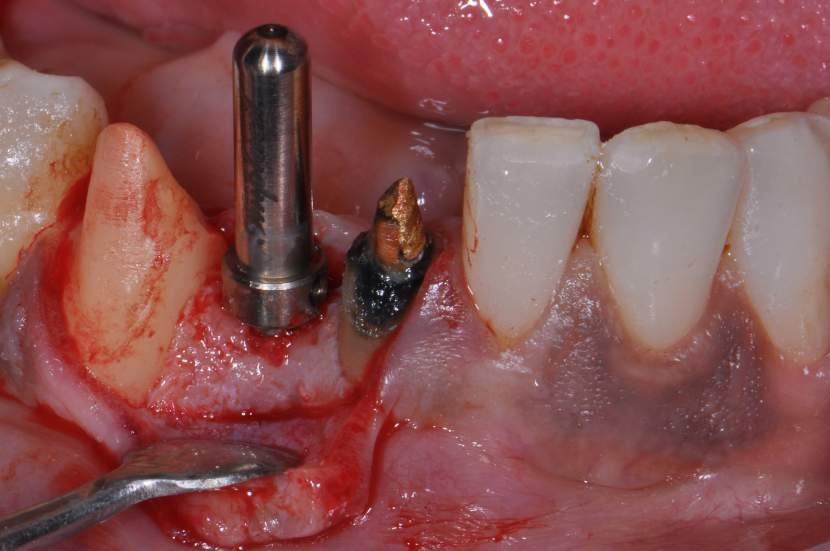

O implante Slim Pilar de corpo único com os diâmetros de 2,5 e 3,0 milímetros (Fig. 2) foram desenvolvidos para superar o desafio de pequenos espaços desdentados.

Um implante de corpo único não tem interface entre o corpo do implante e pilar protético, e, por conseguinte, a perda óssea crestal inicial e ao longo do tempo pode ser reduzida. 5,6

TÉCNICA CIRÚRGICA

O procedimento cirúrgico para os implantes Slim segue um protocolo semelhante como outros implantes, porém muito simplificado. Normalmente utilizase a técnica anestésica infiltrativa. Um retalho mucoperiosteal deve ser rebatido para uma observação direta do rebordo ósseo disponível. No entanto, quando o tecido queratinizado e o volume ósseo abundantes estiverem presentes, uma cirurgia flapless é muitas vezes o protocolo cirúrgico de escolha.2

Para instalação de implantes de Ø 2.5mm é necessário apenas a utilização da fresa lança diâmetro de 2.0 mm. E para instalação de implantes de 3.0 mm utilização da fresa lança diâmetro de 2.0 mm e opcionalmente a fresa Countersink Slim 3.0mm (em casos de osso tipo I ou tipo II). O implante tem o ápice cortante e espiras que facilitam sua instalação. Os implantes Slim se apresentam de 1 em 1 mm de comprimento de 7 a 13 mm, o que facilita muito a escolha dos tamanhos no momento do planejamento.

CASO CLÍNICO

Paciente com perda do incisivo central inferior do lado direito, utilizando uma prótese fixa em zircônia com estética e adaptação deficientes.